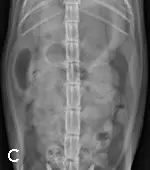

A) Right radiograph, B) Left radiograph, and C) Ventrodorsal radiograph

Abdominal radiography: Left/right lateral and VD views.

Radiographic Findings: The stomach (St) and duodenum (D) are severely distended with fluid and gas, suggesting intestinal obstruction or possibly pancreatitis with secondary ileus.

There is a 1.5-cm rounded opaque structure (arrows) in the caudal abdomen, to the left of the descending colon on the VD view. It is partially obscured by feces in the colon (C) on the left lateral view. The remaining organs and serosal detail appear normal.